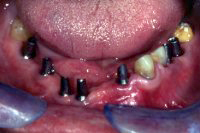

Im Unterkiefer habe ich einige parodontal schwer geschädigte Zähne gezogen und zwei Monate später sieben Implantate gesetzt, wobei bei einigen kleinere Augmentationen gemacht wurden (advanced implantology). Nach sechswöchiger Einheilung der Implantate (Abb. 5 und 6) wurden die Aufbauten in die Implantate eingeschraubt und die verschiedenen Brücken festsitzend zementiert.

Abb. 7 zeigt das Resultat im Unterkiefer nach der Sanierung. Im Oberkiefer läuft dieser Fall unter komplexer Implantologie als Fall 8 weiter.